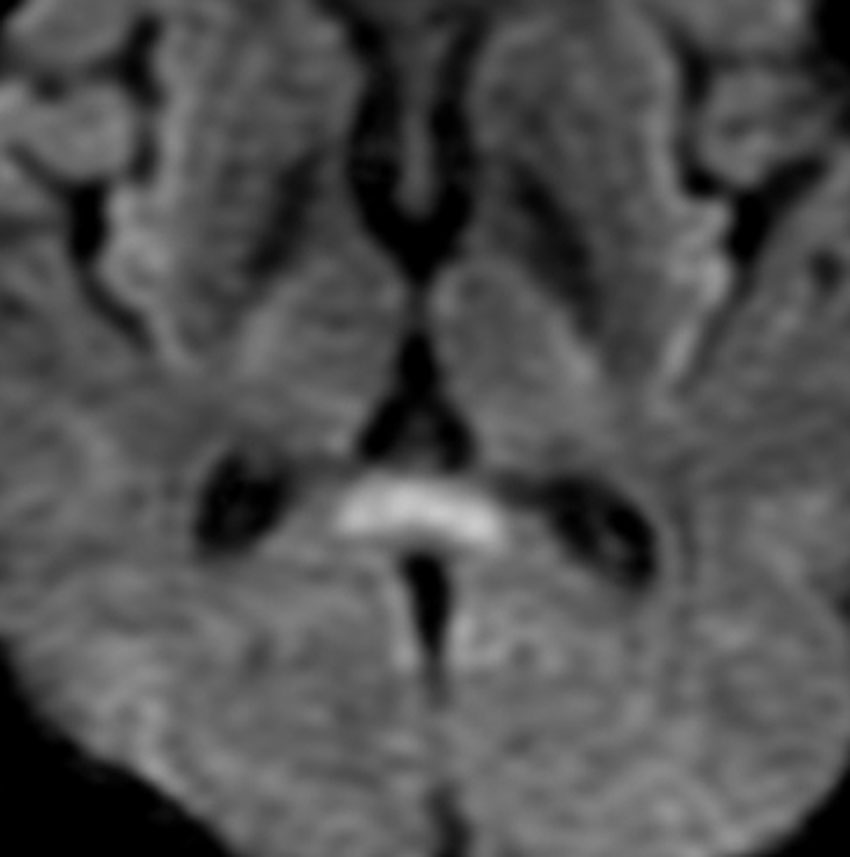

てんかんの薬を止めた時のMERS

mild encephalitis/encephalopathy with a reversible isolated SCC (splenium) lesionといいます。グリオーマの患者さんで予防的に抗てんかん薬を処方することは多いです。腫瘍が落ち着いて長くてんかん発作がない時には,抗てんかん薬を中断します。その時に,MRIで脳梁膨大部 splenium というところに異常な初見が出てグリオーマの再発と間違うことがあります。でもこれはMERSという一時的な病変で,何もしないでも消失します。

左が拡散強調画像 DWIで脳梁膨大部が高信号で白く見えます。右はFLAIR画像でよく見るとちょっとだけ白く見えます。この例はとても軽い初見でDWIでしかはっきりしませんが,通常はFLAIR画像で楕円形の病変としてみられます。

間脳下垂体障害で低ナトリウム血症になると,MERSが生じることもあります。